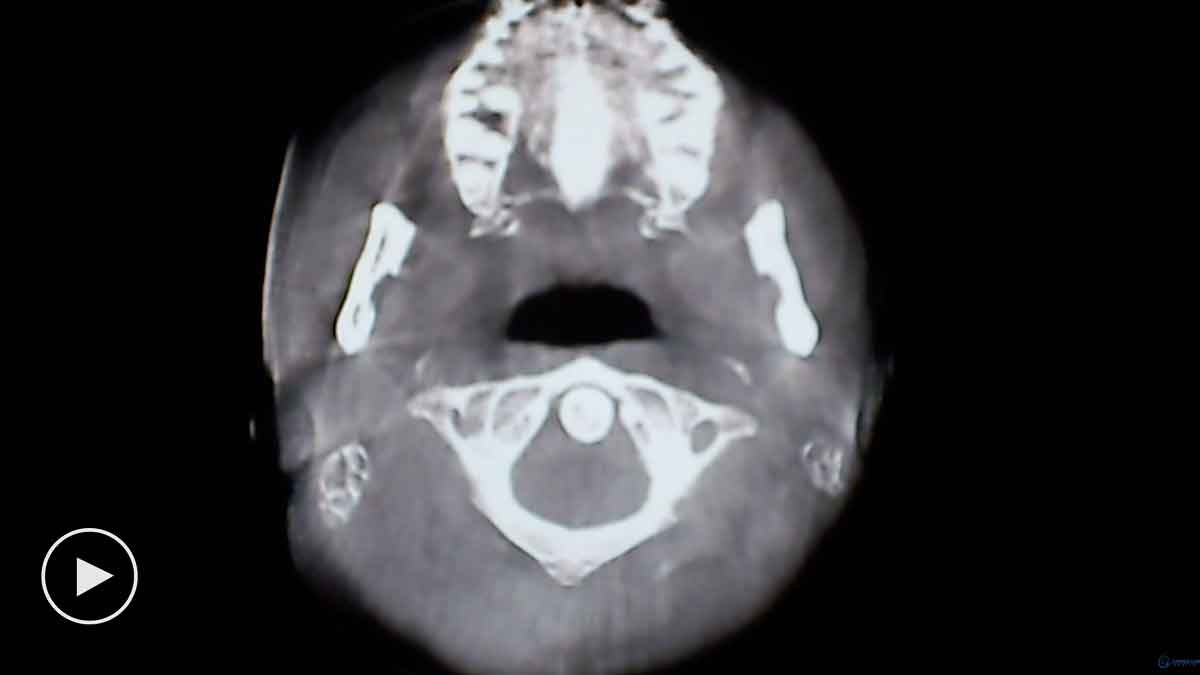

AXIAL VIEW OF FORAMEN MAGNUM AND ATLAS

This view allows the doctor to study the alignment of the upper cervical spine in a traditional APOM view. In chiropractic, the APOM is viewed from the posterior to the anterior to keep left and right right.